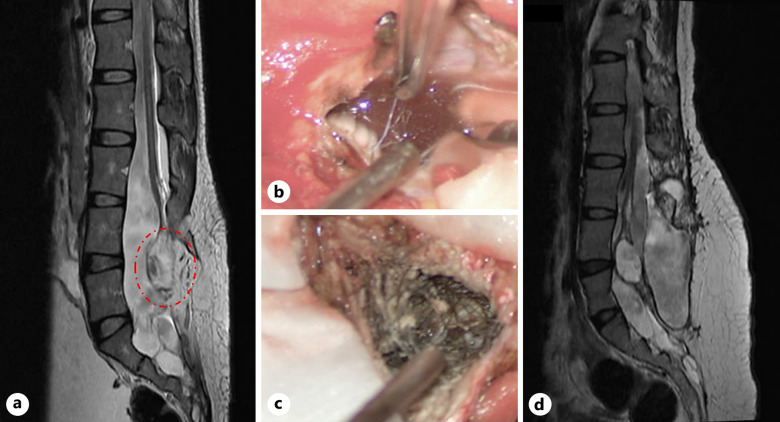

Case presentation: A 31-year-old Asian male patient suffering from epileptic onset and poor antiepileptic treatment was demonstrated. The spinal imaging examination was performed, and the patient suffered a space-occupying lesion within the conus medullaris related to spinal deformity, spinal embolism, etc. The autoimmune encephalitis spectrum revealed mGluR5 antibody IgG (+) 1:10 response. The patient stabilized after treatment with hormones and human immunoglobulin. Some hair and lipid droplets could be observed in the dural sac intraoperatively, and more hair and lipid-like material were present in the spinal cord. Postoperative pathology established the diagnosis as a conus medullaris teratoma in adults. Epileptic seizures stopped after surgery, and no additional seizures were reported during the 33-month follow-up period.